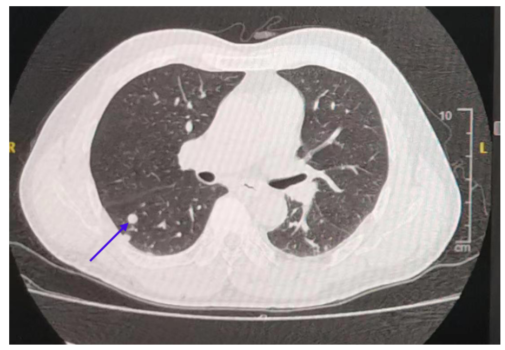

2016.07-2017.01:行XELOX方案辅助化疗6周期 + 卡培他滨2周期后停药。2018.07:复查CT提示新发肺部转移灶(图1)